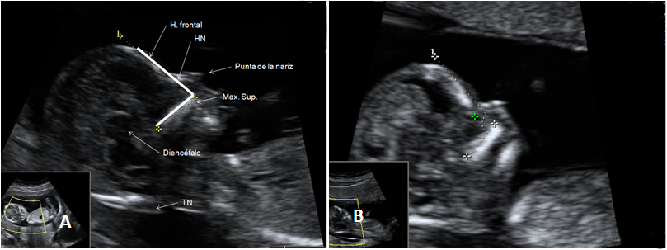

Ecografía Embarazo 4D Semana 12 - PRUEBAS DIAGNÓSTICAS